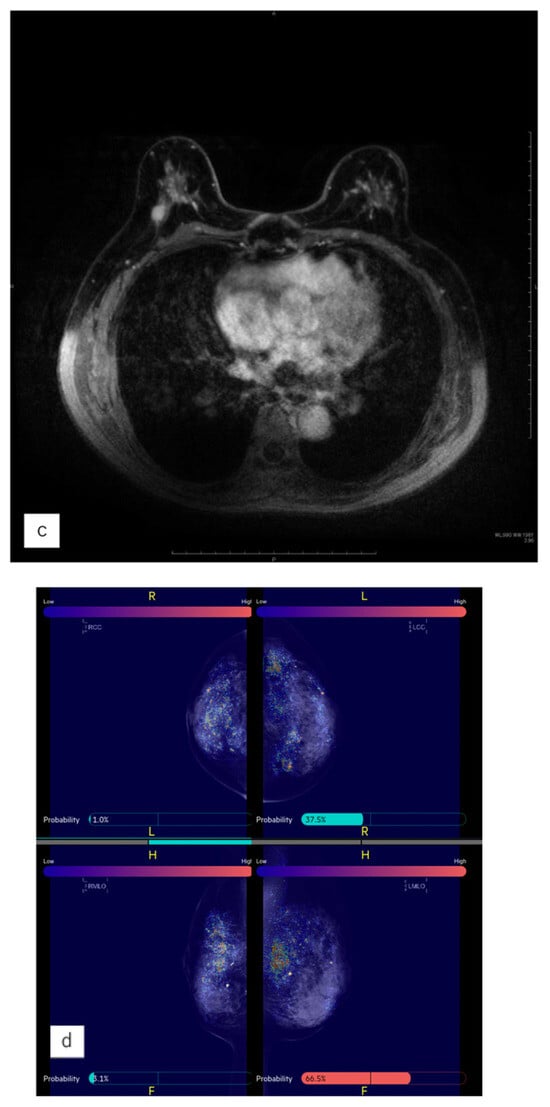

We used the MG AI system FxMammo® (FathomX Pte Ltd., Singapore). The AI system is based on deep learning and has been put into practical use in Singapore and other countries. The mechanism of FxMammo has been described in previous studies. The AI system is based on the VGG-16 network [20]. The VGG network is one of the most used feature extractors in medical imaging classification [21]. The AI was created by collecting 17,769 cases (of which 45% were malignant) from 10 institutions in Taiwan, Thailand, Singapore, Hong Kong, China, Malaysia, and Japan. Since 2019, we have been collaborating with the National University of Singapore to develop MG AI for Asian women. This AI model, which utilizes CNNs and graph convolutional networks, quantifies the probability of malignancy and highlights areas of interest on a heat map when mammography images are uploaded. The model demonstrated a high Area Under the Curve (AUC) of 0.902 for BC detection [22]. If we assume a cancer miss rate of 3%, it is estimated that up to 38% of normal MG could be safely excluded from human review. In Japan, the AI system has not been approved for clinical use and it is used for research purposes. Four MG images (craniocaudal [CC], mediolateral oblique [MLO], left, and right) taken before surgery for heterochronic contralateral BC were transferred from the reporting system to the AI system where the MG data were analyzed. The threshold value was set to 40.0%, (91.5% sensitivity and 82.0% specificity). The AI system indicated the probability of malignancy for each of the four cards as a percentage. In addition, areas in which the AI system was interested were displayed in color on a heat map. The areas on which the AI system focused when analyzing the image are visually shown as a heat map (Figure 2).

Figure 2.

Displaying images in FxMammo. An image of the mediolateral oblique of mammography is shown on the left. A spiculated mass is seen in the left upper area. On the right is the result of the AI system analysis, with the areas of interest to the AI system indicated by the colors in the heatmap. The malignancy percentage is shown on the left and right sides, respectively (right: 3.3%; left: 94.2%).